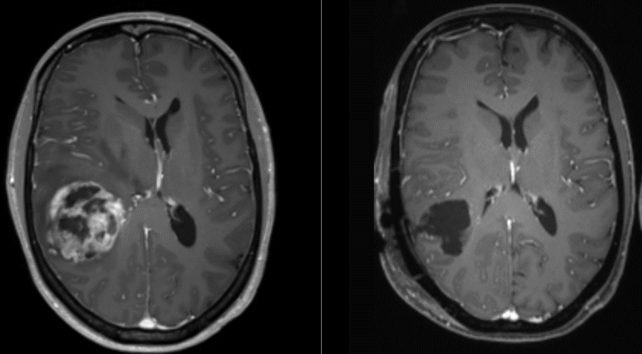

MRI Image of a Glioblastoma before and after surgery

Surgery is currently the first stage of glioblastoma treatment. (Ars Neurochirurgica/Wikimedia/CC 4.0)